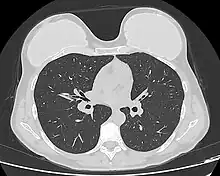

Computed tomography of a woman with breast implants

Implant rupture visualized by breast computed tomography

Because a breast implant is a Class III medical device of limited product-life, the principal rupture-rate factors are its age and design; nonetheless, a breast implant device can retain its mechanical integrity for decades in a woman's body.[43] When a saline breast implant ruptures, leaks, and empties, it quickly deflates, and thus can be readily explanted (surgically removed). In some cases, saline implant rupture can result in an infection due to bacteria or mold that had been within the implant, though this is uncommon.[44] The follow-up report, Natrelle Saline-filled Breast Implants: a Prospective 10-year Study (2009) indicated rupture-deflation rates of 3–5 per cent at 3-years post-implantation, and 7–10 per cent rupture-deflation rates at 10-years post-implantation.[45] In a study of his 4761 augmentation mammaplasty patients, Eisenberg reported that overfilling saline breast implants 10-13% significantly reduced the rupture-deflation rate to 1.83% at 8-years post-implantation.[46]